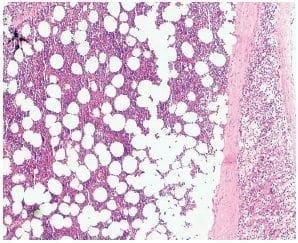

Figura 4. Mielolipoma subyacente al tejido cortical suprarrenal normal. Hematoxilina y eosina, 4X.

Figura 5. El mielolipoma suprarrenal está constituido por tejido adiposo maduro, mezclado con componentes hematopoyéticos. Hematoxilina y eosina, 10X.